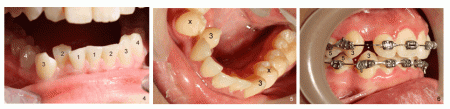

一位中國女孩八歲提早失去一顆下頜乳尖牙(圖一至圖三:*,與對側乳尖牙(C)對比),正常情況下,這顆牙齒應該十一歲左右脫落。過早脫落會造成鄰牙(中切牙(圖一、圖二:1)和側切牙(2)移位(<),乳尖牙空間關閉(圖一至圖三:*),下面恆尖牙(圖三:3)便沒有空間在正常位置萌出(^)。原本應該及時做早期牙齒矯正,讓移位牙齒復位,而且為以後恆尖牙萌出創造空間。

這微小變化容易被忽略,一晃四年過去了,患側恆尖牙從唇側(牙弓外側)萌出(圖四:3),而側切牙(2)被推到舌側(牙弓內側),現在矯正麻煩多了。

另外一例:尖牙因為沒有空間在舌側萌出(圖五),為了解決空間問題,尖牙後面兩個下頜前臼齒必須拔除(圖五:x,也就是圖三圖四:4),為了達到上下牙弓匹配,上頜兩個前臼齒也需要拔除。矯正一年後,下尖牙已經恢復正常位置(圖六:下面#3),但是一側失去兩個第一前臼齒(4)。如果早期矯正,我們可能避免後期矯正時需要拔除四個牙齒問題(1 、2 、3)。